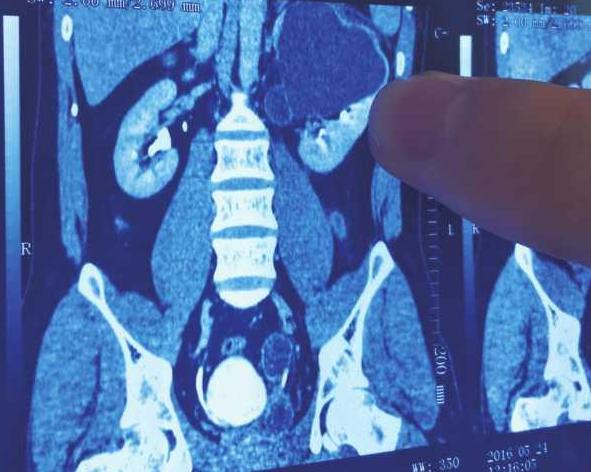

虽然雷先生一直坚持是因为结婚后发福了,可在家人的一再催促下,他还是来到了医院检查,医生在给雷先生的大肚子做了彩超后,大吃一惊,虽然雷先生的肝脏和胃都正常,但是他竟然有4个肾脏!

这种病学名叫做:先天性双侧双肾、双输尿管重复畸形。每10万个人中才有1例。

雷先生的右侧一个肾脏的输尿管没有接入膀胱,呈闭锁状态,这就造成了大量的尿液在输尿管里聚积,如果一旦发生破裂导致感染,严重的会危及生命。